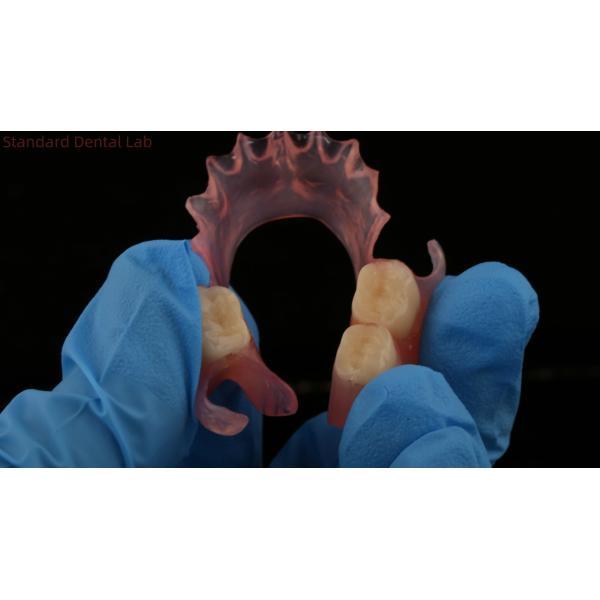

Dental TCS Valplast Flexible Partial Dentures Nesbit Valplast Finish China Dental Lab

Nesbit Valplast is a specific type of partial denture that is made using the Valplast material. Nesbit dentures are designed to replace one or more missing teeth in a specific area of the mouth. They are known for their flexibility, durability, and natural appearance.

The "finish" of a Nesbit Valplast denture refers to the final surface treatment or polishing applied to the denture to enhance its aesthetics and smoothness. The finish process helps to create a more natural-looking denture that blends seamlessly with the surrounding teeth and gums.

The finishing process for Valplast dentures typically involves various steps, including trimming excess material, smoothing rough edges, and polishing the surface. This is done to ensure the denture is comfortable to wear, fits properly, and provides an aesthetically pleasing result.

To achieve a high-quality finish for a Nesbit Valplast denture, it is important to have it fabricated by a skilled dental technician or dental laboratory that specializes in working with Valplast material. These professionals have the expertise and experience to handle the material properly and apply the necessary finishing techniques to create a well-finished denture.

| 3 | Nesbit Valplast Finish |

Dental TCS Valplast Flexible Partial Dentures Nesbit Valplast Finish China Dental Lab Valplast Clasp Images |